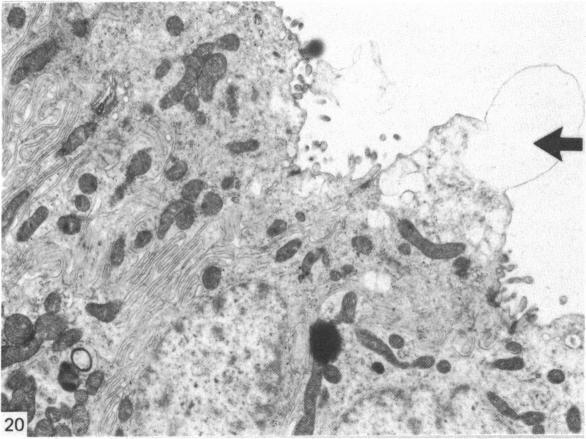

The kidneys of the green turtle are flattened, lobed and closely applied to the posterior wall of the pleuroperitoneal cavity. The ability to differentiate new functional nephrons is retained by five years old animals. The functional nephron comprises a glomerulus, proximal tubule, intermediate segment which can be subdivided into a proximal non-secretory segment and a distal mucus secreting segment, distal convoluted tubule and collecting tubule. Both the proximal and distal tubules exhibit complex foldings on their lateral cell walls in contradistinction to the characteristic basal infoldings observed in mammalian tubules.

绿海龟的肾脏扁平、呈叶状,紧密贴附于胸膜腹膜腔的后壁。五岁的绿海龟仍保留分化出新的功能性肾单位的能力。功能性肾单位由肾小球、近端小管、中间段(可细分为近端非分泌段和远端黏液分泌段)、远端曲管和集合管组成。与哺乳动物肾小管中典型的基底褶不同,近端和远端小管的外侧细胞壁均呈现出复杂的褶皱。